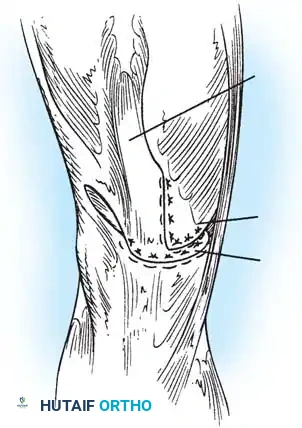

Fig. 45-16B: The quadriceps tendon is drawn distally and sutured directly to the patellar tendon. The vastus medialis is then advanced distally and laterally, imbricating it over the midline repair to centralize the tracking vector and reinforce the extensor mechanism.

4. Vastus Medialis Advancement: Mobilize the vastus medialis obliquus (VMO). Advance it distally and laterally over the primary repair site. This V-Y type advancement not only thickens the repair but restores the dynamic medial stabilizing force lost during patellectomy.